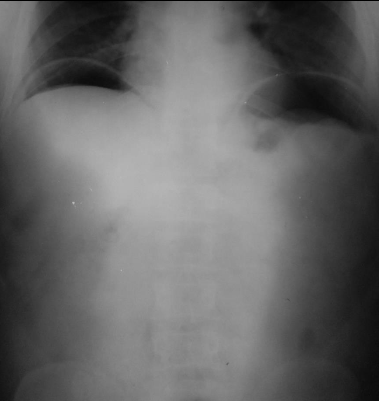

Pneumoperitoneu